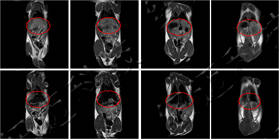

儀器使用小動(dòng)物核磁共振成像系統(tǒng),圖像為T1加權(quán)像橫斷面、冠狀面,采樣參數(shù)如下:FOV=100mm×100mm, TR=400ms, TE=19ms, 層厚3.5mm, 層間距1mm, 累加次數(shù)16, K空間大小192×256。成像結(jié)果顯示,注射造影劑后,大鼠心臟與肝臟變亮,且隨代謝時(shí)間延長(zhǎng)逐漸變暗。

大鼠造影前后MRI冠狀面

大鼠體內(nèi)造影劑代謝MRI橫斷面